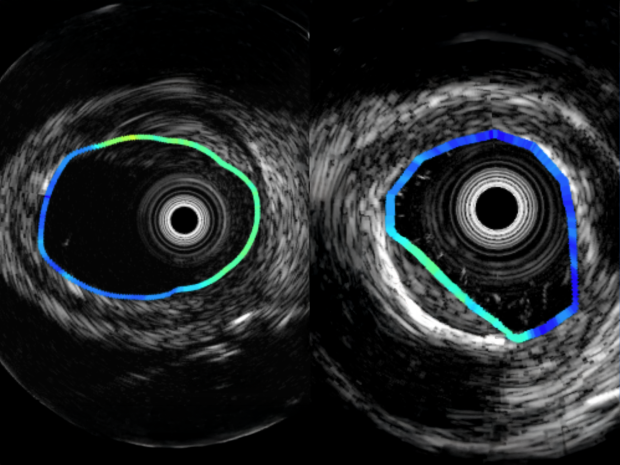

Plaque characterization with intravascular fluorescence lifetime imaging

Plaque characterization with intravascular fluorescence lifetime imaging (adapted from Bee, J. et al. J Am Coll Cardiol lmg. 2021;14(9):1832-1842.)